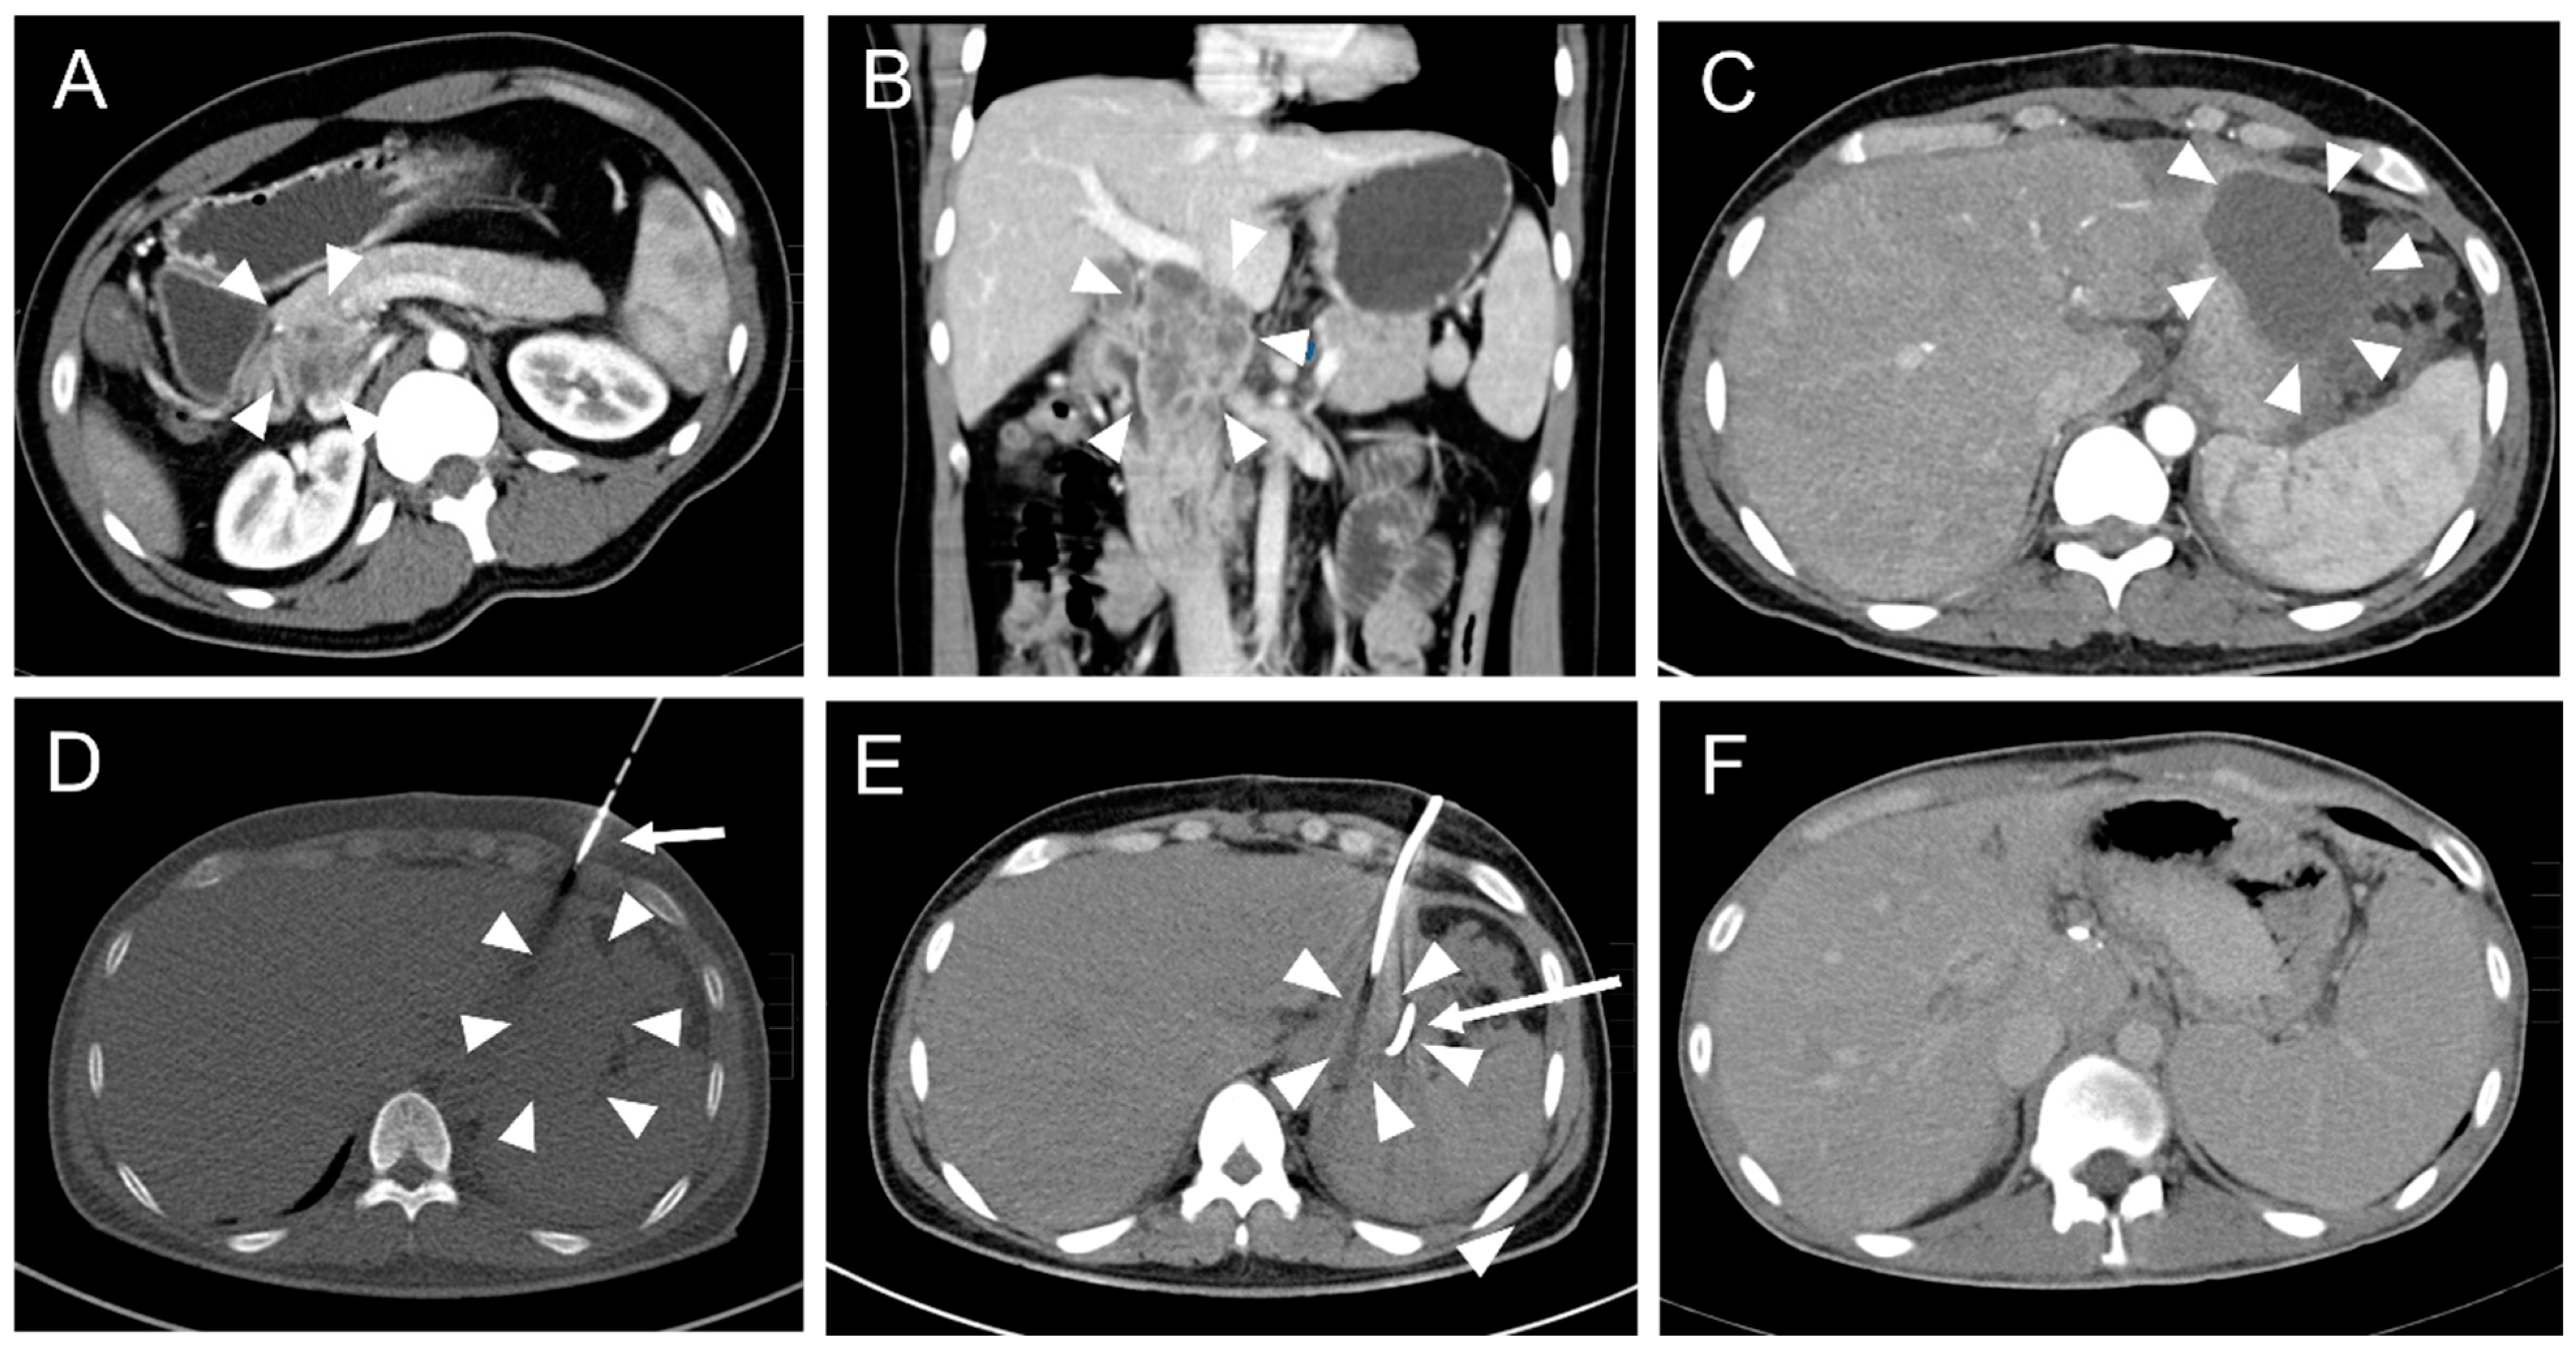

Primary placement of the drainage was successful in 165 interventions (Figure 2).

Figure 2. A typical CT fluoroscopy-guided drainage placement procedure after pancreatic surgery. (A) A 33-year-old male with a history of abdominal tuberculosis and the formation of an inflammatory pseudotumor in the pancreatic head (arrowheads). (B) Coronal reconstruction of the abdominal CT scan illustrates a multicystic mass of the pancreatic head (arrowheads) with close vascular relation to the portal vein and lower vena cava. (C) The patient developed subfebrile temperature and left epigastric pain 19 days after pylorus-preserving pancreaticoduodenectomy (PPPD). CT revealed a left paragastric serous fluid collection (arrowheads). (D) CT fluoroscopic image (10 mAs tube current). An 8F pigtail drainage was inserted into the fluid collection (arrowheads) with the trocar technique using an anterior intercosto-cartilaginary approach (arrow). (E) Post-interventional CT scan. Unenhanced post-drainage (arrow) CT scan showed significantly reduced paragastric fluid collection (arrowheads). Microbiological analysis of the aspirated fluid revealed infection with Serratia marcescens. (F) CT follow-up eleven months later showed complete resolution of the fluid collection. Note the increase of spleen size due to portal vein occlusion with beginning cavernous transformation.